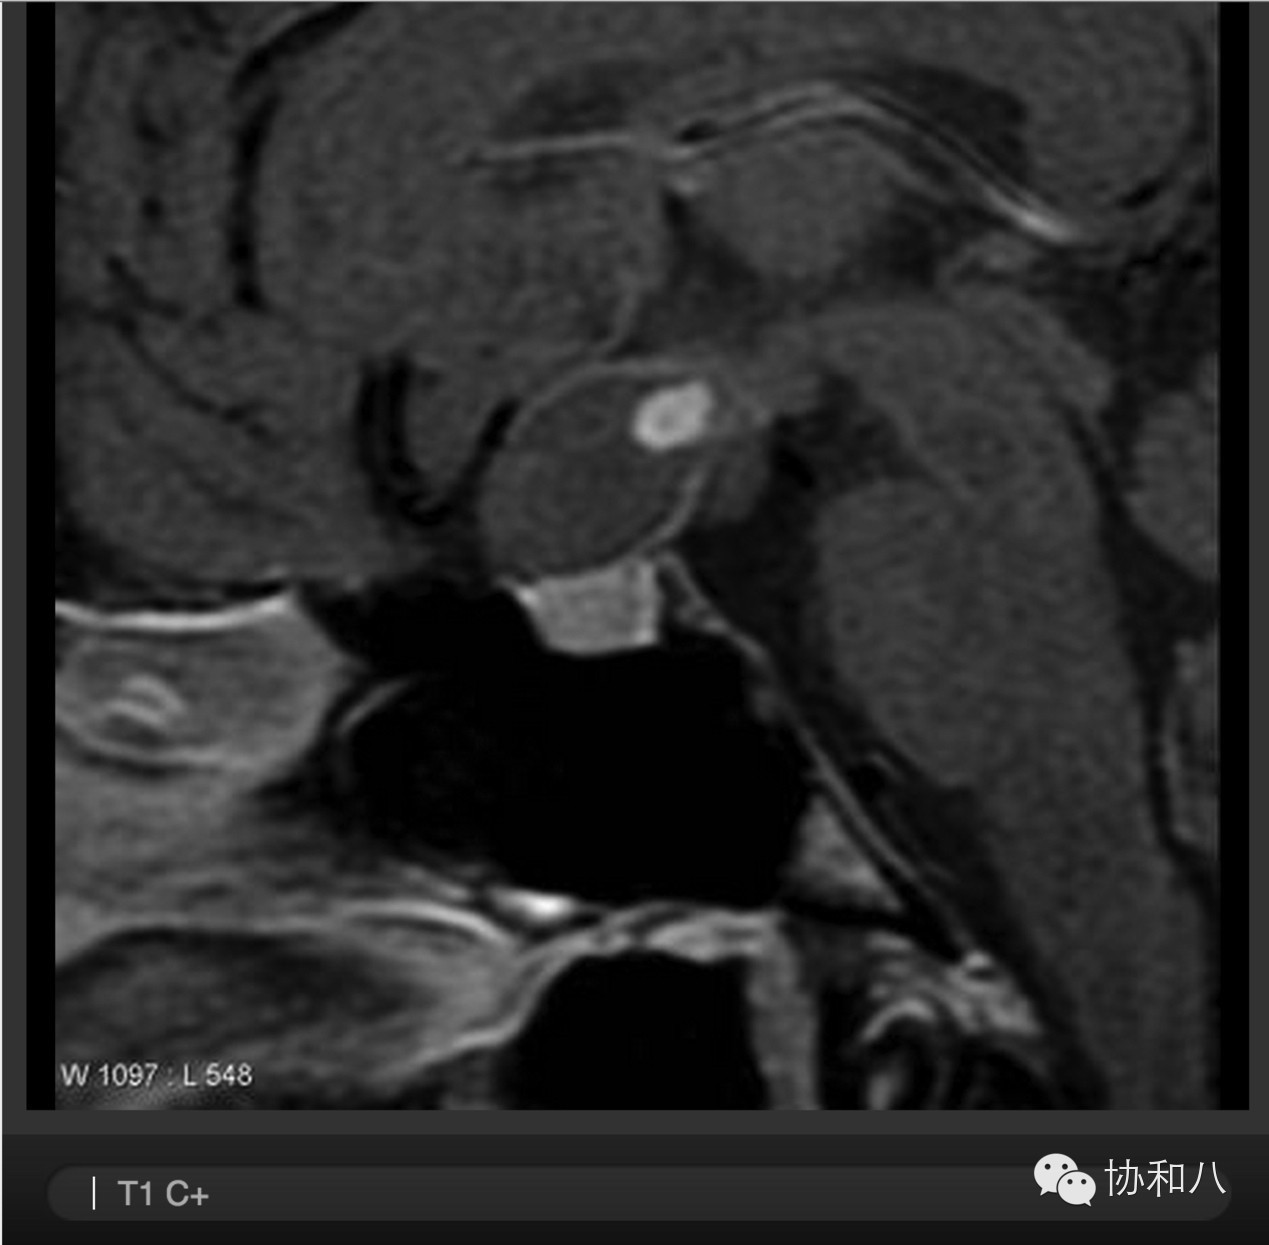

D. 增强冠状位T1WI

可见鞍区占位,T1 C+信号混杂,增强不均匀,符合出血坏死表现。